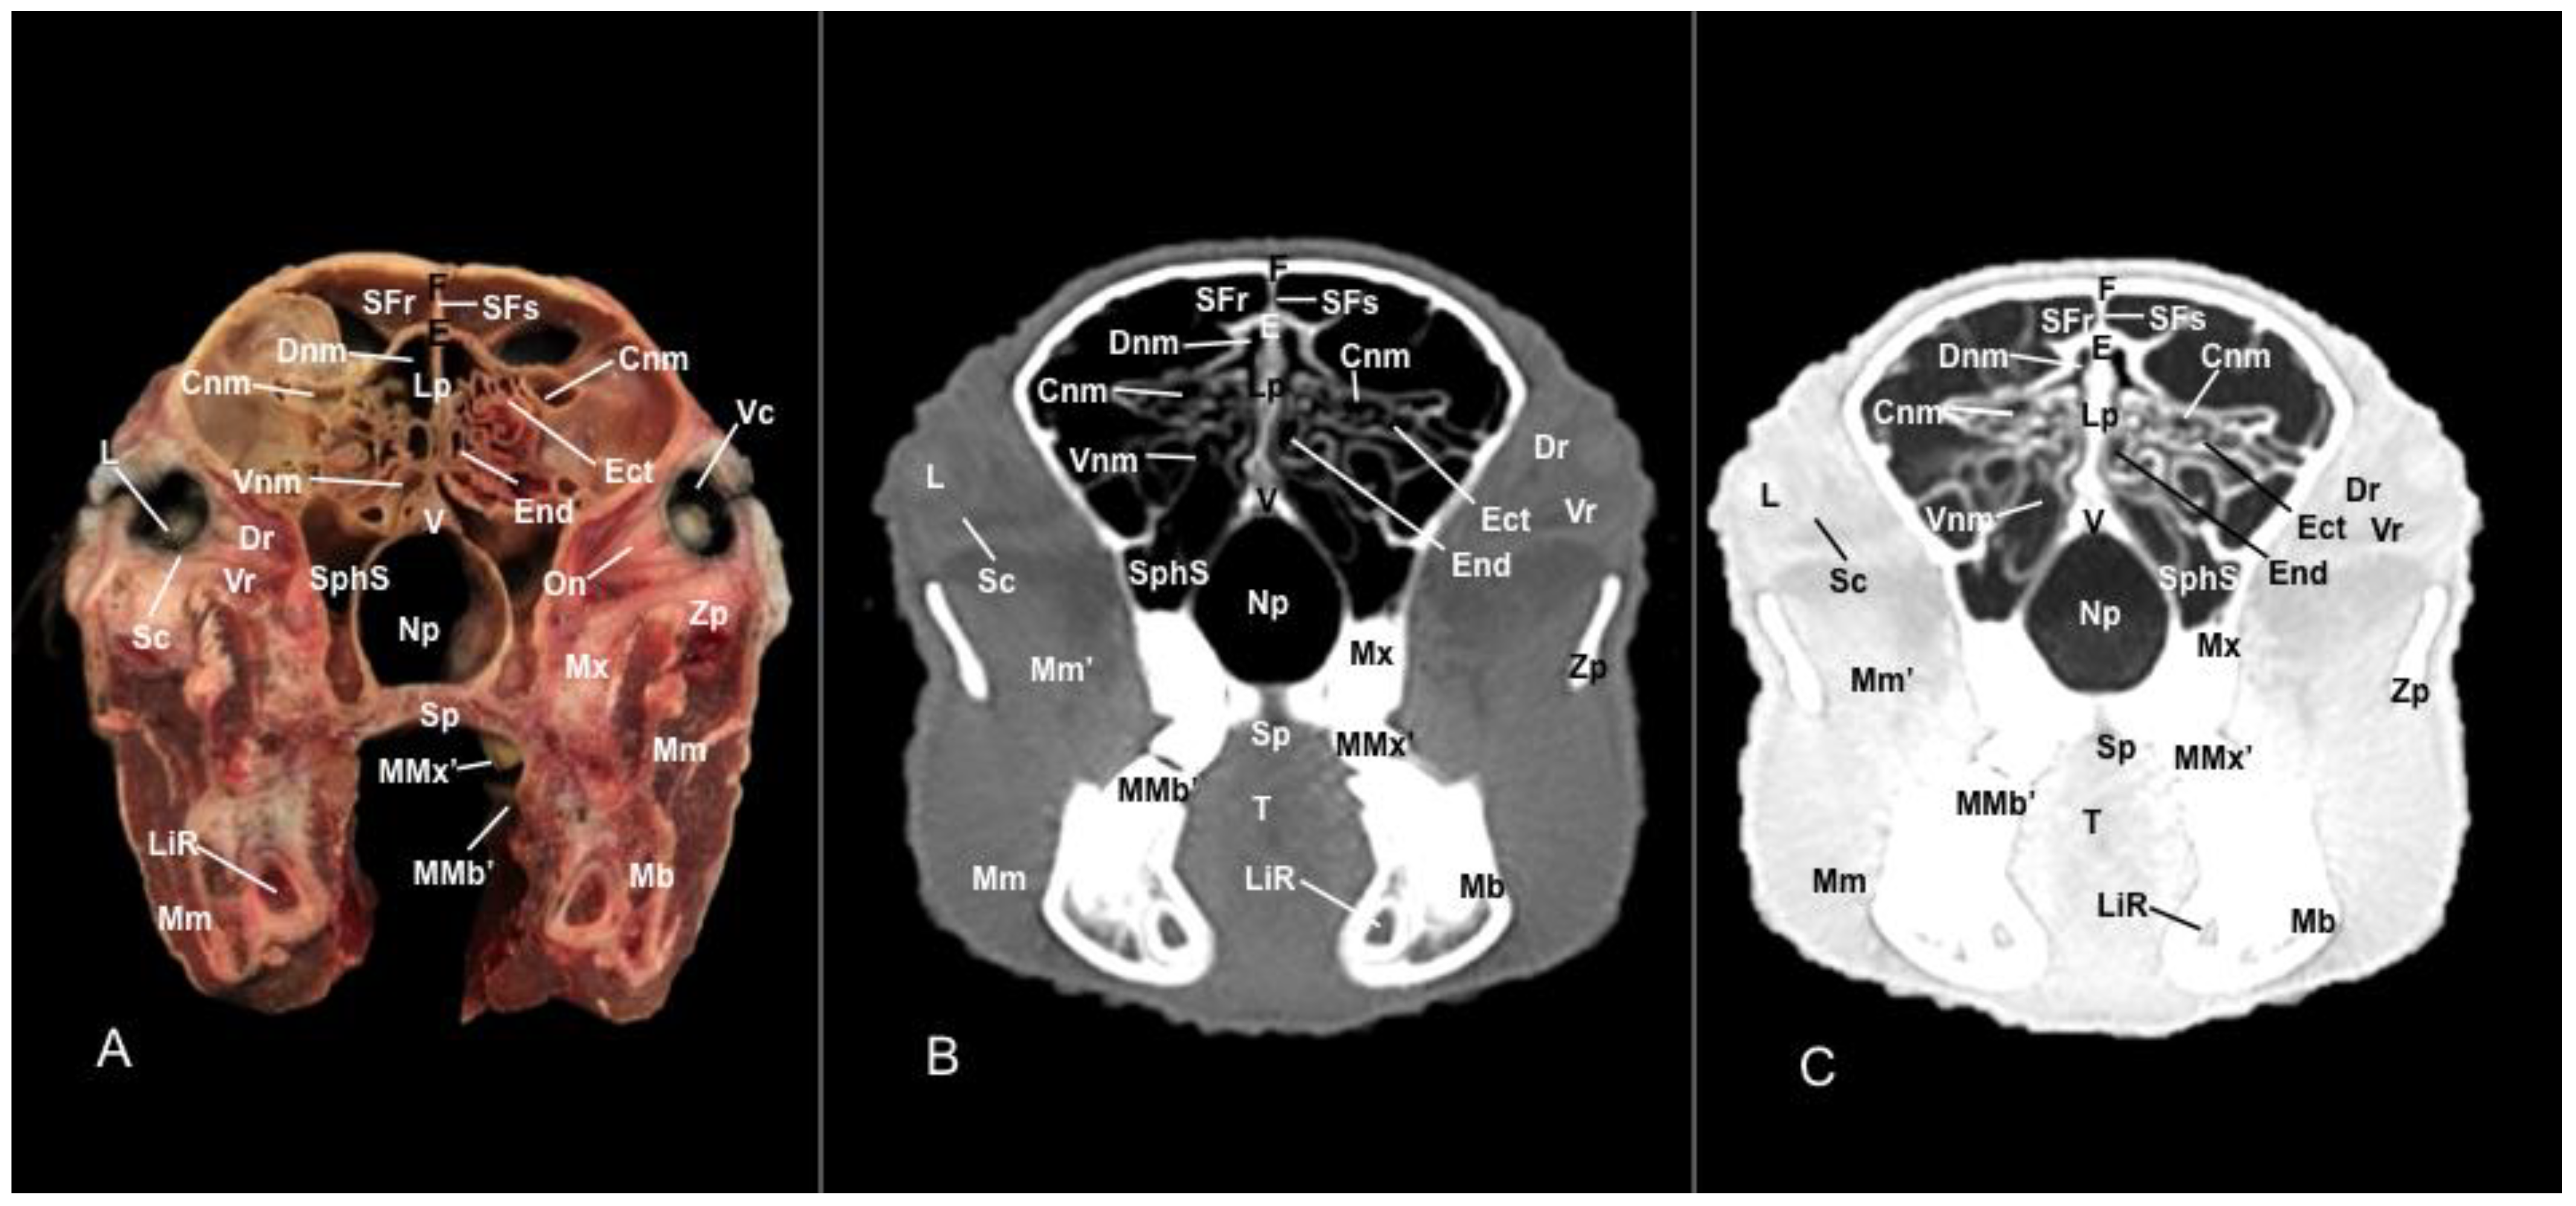

3.1. Anatomical Sections

3.2. Computed Tomography (CT)